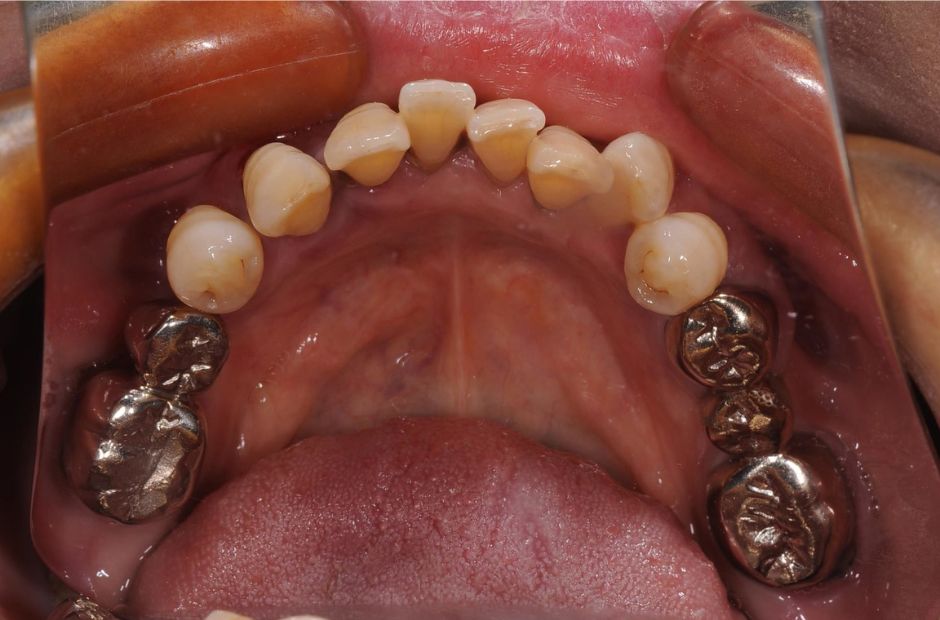

case.04

他院で断られた症例の成功

他院でインプラント治療が困難とされた高齢の患者様が当院に来院されました。複雑な口腔状況でしたが、当院の専門知識と技術を活用してインプラント治療を成功させました。治療により、患者様は再び快適な食事と明確な発音を取り戻すことができました。